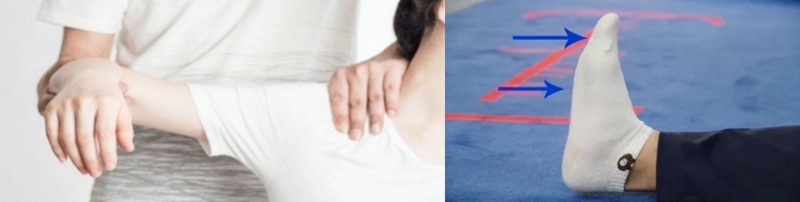

L5神经根定位的主要标志性表现之“足下垂”

Foot drop(足下垂):是指脚背抬高时足部无法向上抬起,导致足部处于下垂状态的情况。(足背屈肌无力)足下垂时因小腿前部肌群无力,足无法上抬,走路时病人被迫只能将患肢大幅度抬高,才能使患肢足完全离地。

临床表现

患足背伸无力,表现为足下垂畸形,伴或不伴小腿或足背脚趾I-III感觉改变。足背屈、足趾伸展、足外翻和第一蹼间隙感觉丧失无力。踝关节外翻无力。

查体:踝背伸及踇趾背伸肌力3级以下,合并小腿外侧或足背皮肤痛觉减退。

(1)运动疗法

踝关节活动度的维持,肌肉萎缩的预防,肌力及耐力训练,借助足托进行渐进性步行训练。